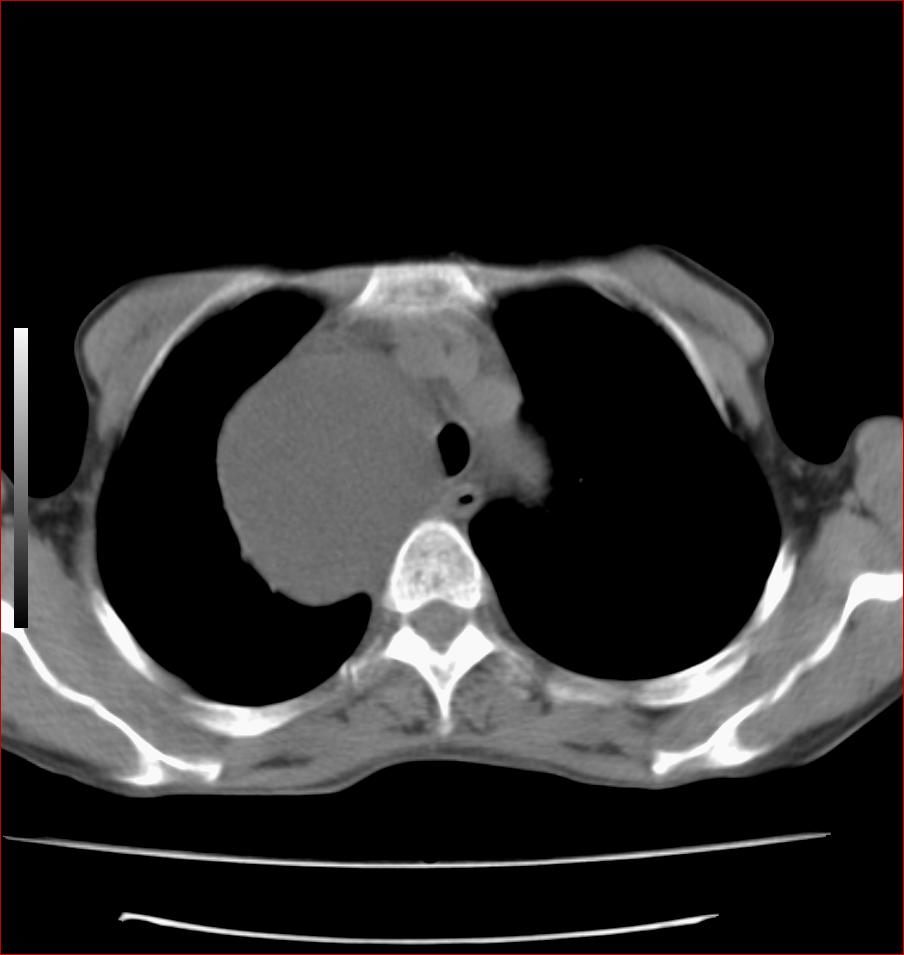

标题: CT17110:F56Y,纵隔囊肿;胸腺?淋巴?请各位老师看看 [打印本页]

女性患者 56 咽痛伴声嘶10+天入院。

右上纵隔囊性占位性病变;考虑支气管囊肿可能。

病变紧贴气管右壁,两者相互压迫,考虑支气管囊肿!

见相互挤压征,考虑气管囊肿,建议ct增强扫描

右上纵隔囊性占位性病变;考虑支气管囊肿可能。建议ct增强扫描

纵隔前肠性囊性,支气管囊肿可能性大